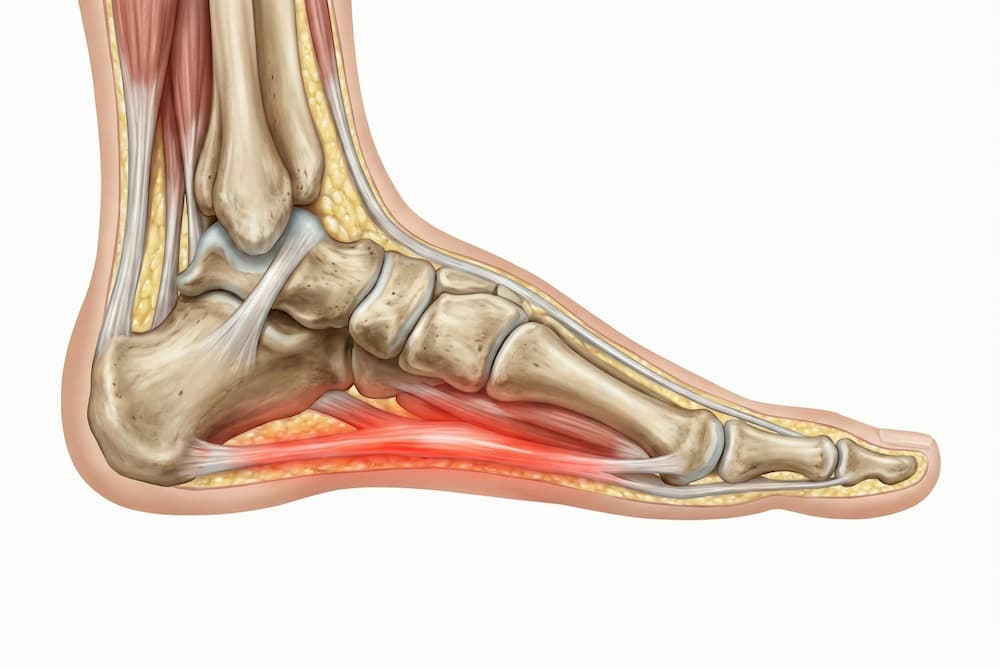

- Plantar fasciitis: Betændelse i plantar fascia (senebåndet, der løber langs fodsålen).

Plantar fasciitis er en almindelig årsag til smerter, som jeg ofte ser i behandlinger. Jeg anbefaler strækøvelser og stødabsorberende indlægssåler for at lindre smerterne og fremme helingen.